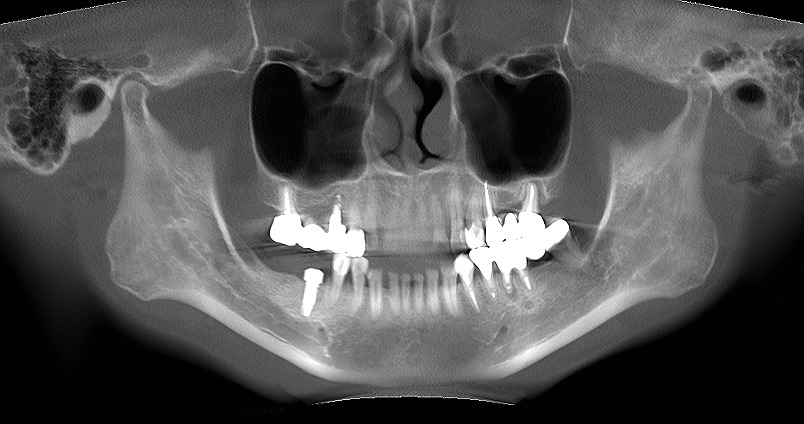

埋入前と埋入後のパントモになります

神経までの距離がないことがうかがえます

10mm以上のインプラントでなければインプラントは埋入しないことにしています

埋入後になります